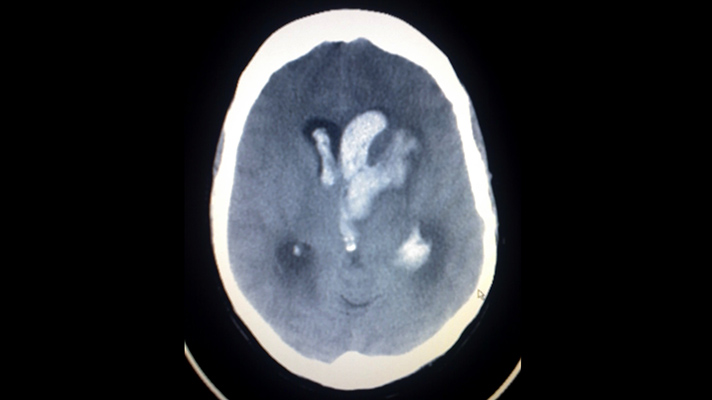

IBM Watson Health and Israel-based MedyMatch Technology are joining their AI forces in hospital emergency rooms to help doctors detect intracranial bleeding resulting from head trauma and stroke. The MedyMatch algorithm uses deep learning, machine vision, patient data and clinical insights to automatically highlight for a physician areas that might indicate the potential presence of cerebral bleeds.